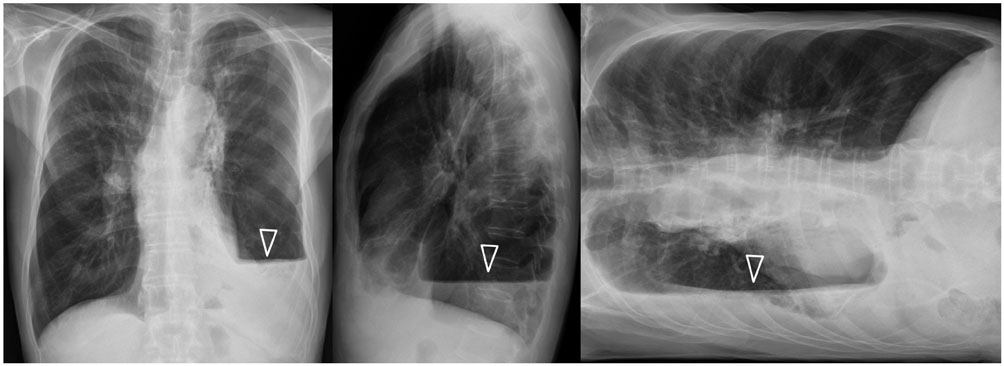

코로나 바이러스 감염증 (COVID-19)은 호흡기 질환으로, CT 스캔은 폐에 초점을 맞춘 이미지를 제공하여 질병 진단에 중요한 역할을 합니다. 이러한 CT 상에서는 폐섬유화증이 나타나는 임상적인 특징을 확인할 수 있습니다. 폐섬유화증은 폐 조직의 섬유화가 진행되어 폐 기능을 저하시키는 질환입니다.

코로나 폐 CT에서 폐섬유화증을 확인하기 위해 특정한 임상적인 특징을 주목해야 합니다. 폐섬유화증은 다음과 같은 특징으로 나타납니다:

- 신체의 대칭성을 유지하지 못하는 비정상적인 패턴: 코로나 폐 CT 상에서 폐섬유화증은 대칭성을 유지하지 않는 비정상적인 패턴으로 나타납니다. 이는 해당 부위가 코로나 바이러스에 의해 영향을 받았음을 시사합니다.

- 낭포성 반점의 형성: 폐섬유화증은 CT 상에서 낭포성 반점의 형성을 보입니다. 이러한 반점은 폐 조직의 질환과 관련된 염증과 관련이 있을 수 있습니다.

- 기간에 따라 진행되는 변화: 코로나 폐 CT에서는 폐섬유화증이 병력에 따라 진행되는 변화를 보입니다.

처음에는 영향을 받은 부위와 그 외의 부위에 차이가 있을 수 있으며, 시간이 지남에 따라 폐섬유화증이 퍼질 수 있습니다.

폐섬유화증은 코로나 폐 CT에서 확인할 수 있는 임상적인 특징이며, 이를 통해 질병의 진단과 치료에 도움을 줄 수 있습니다.

2. 폐 CT 스캔: 코로나 바이러스 감염으로 인한 폐소견을 파악하기 위해 폐 CT 스캔이 사용될 수 있다. 이 방법은 이미지를 통해 폐의 이상 소견을 확인할 수 있으며, 감염 정도를 파악할 수 있기 때문에 코로나 폐 진단에 중요한 역할을 한다. 3. 필요에 따른 혈액 검사: 코로나 바이러스 감염 여부를 확인하기 위해 혈액 검사가 실시될 수도 있다.